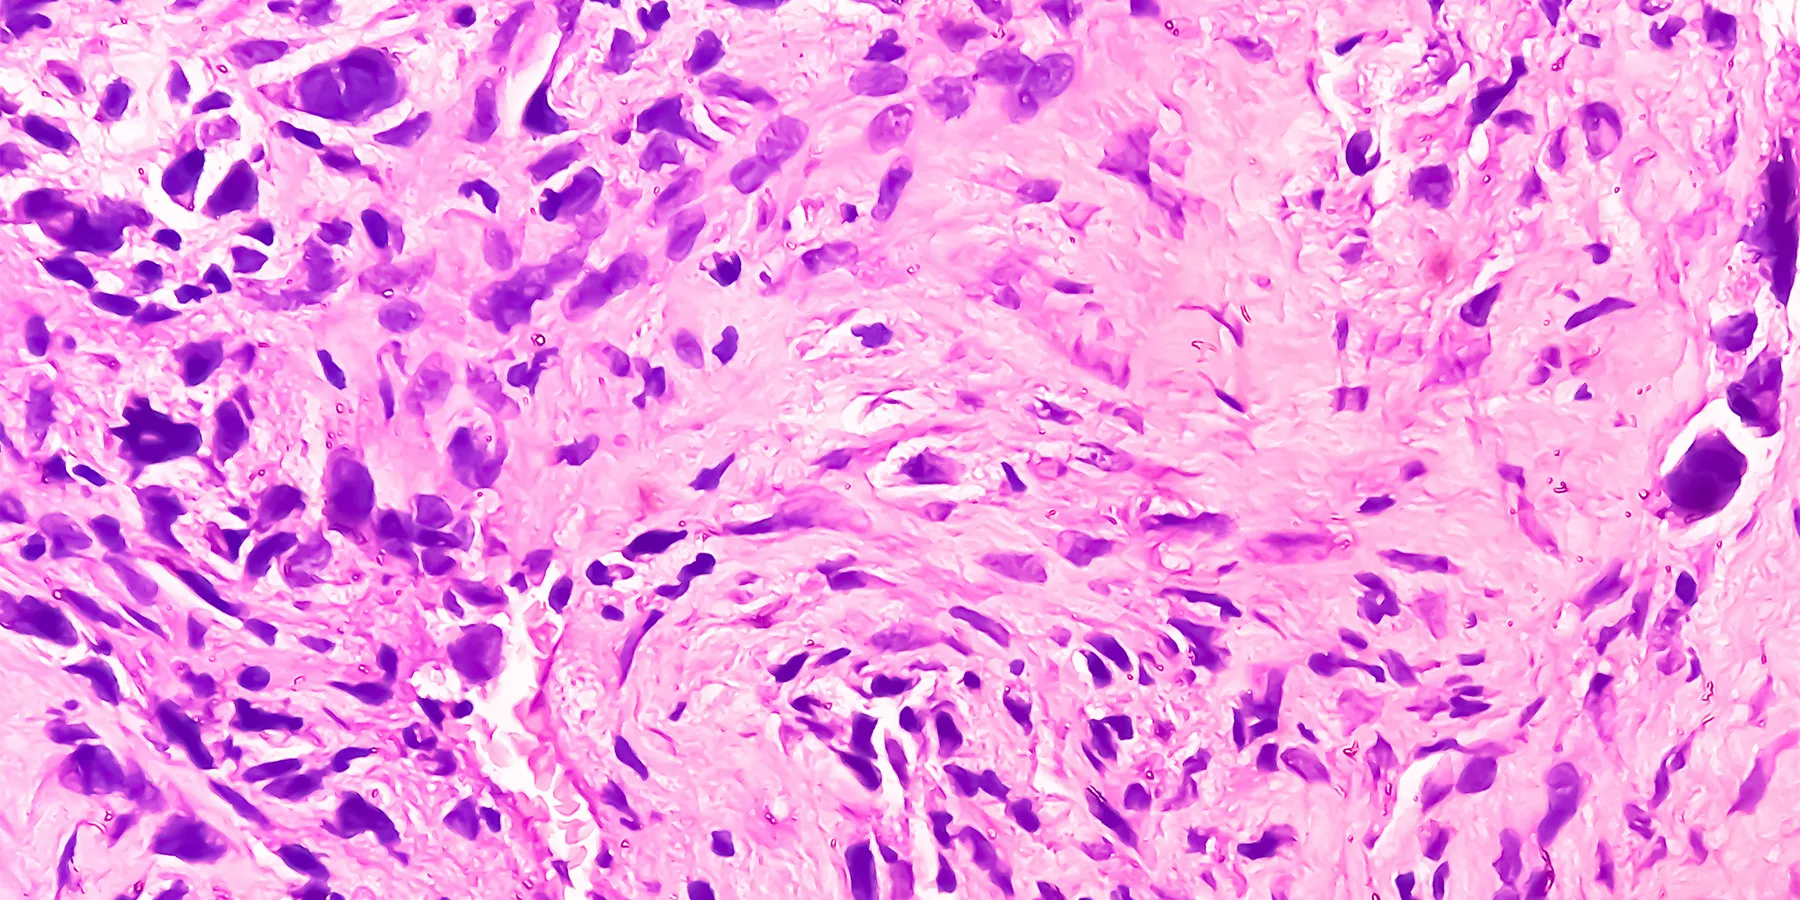

Although osteosarcoma and Ewing sarcoma are the two most common bone tumors of childhood and adolescence, survival rates remain low, especially in older children and those with metastatic disease. In a statement issued on July 15 in Clinical Cancer Research, a group of scientists from the Fight Osteosarcoma Through European Research and Euro Ewing consortia highlighted the lack of high-quality samples for research and clinical trials, pointing to issues such as the overall rarity of these cancers, challenges with tissue collection and processing, and the absence of standardized protocols for sampling these tumors.